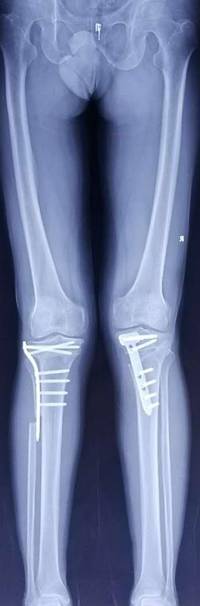

胫骨高位截骨治疗膝关节骨关节炎

优点:创伤小,疗效确切,适合生活方式活跃的年轻患者。

术前术后对比